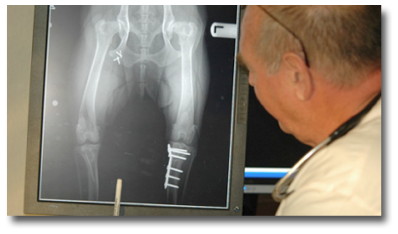

Fracture Repair

For this discussion a fracture is a broken bone as a result of injury or trauma. The repair or reconstruction to normal use of the broken bone can be reasonably straight forward to very complex.

TPLO

Dr. Leadbeater has performed over 500 TPLO procedures , with an exceptional success rate. If your pet has experienced any sudden hind leg pain or lameness, or you simply desire further information on the TPLO procedure, we will be more than happy to schedule a consultation with Dr. Leadbeater.

The knee joint, or stifle joint, in dogs is in most respects very similar to our own. All of the problems that you know occur in our knees also can occur in dogs. These include meniscal injury, anterior, or cranial cruciate tears and ruptures.

The most common cause of sudden onset of lameness in the hind legs of dogs is the tearing of the cranial cruciate ligament. This rupture produces severe instability in the stifle joint, that is inflammatory and painful. Within 4 weeks of an unattended ruptured ligament, x-rays show the beginning of arthritic development.

So what is Tibial Plateau Leveling Osteotomy

Surgical procedures to recreate stability in the joint have changed and evolved over the past 50 years. However, the Tibial Plateau Leveling Osteotomy, or TPLO, has proved to be most successful to date, in correcting the problem and preventing ongoing development of arthritis, when performed by an experienced surgical team.